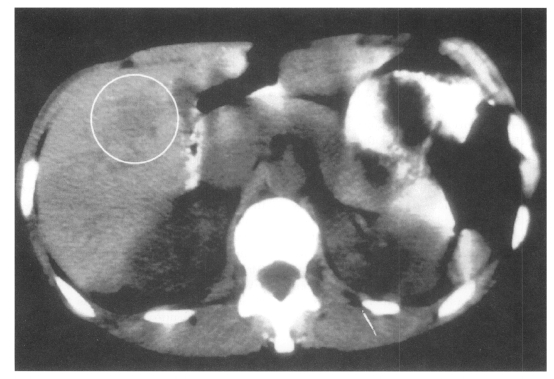

Medical imaging techniques can be used to detect and localize granulomatous lesions due to Toxocara larvae. Abdominal ultrasound has shown multiple hypoechoic areas in the livers of 14 children who initially presented with hepatomegaly, eosinophilia and a positive Toxocara serology (Baldisserotto et al., 1999). Using computed tomography (CT), hepatic lesions appear as low-density areas, as shown in Fig. 1 (Dupas et al., 1986; Ishibashi et al., 1992). In the CNS, more sensitive magnetic resonance imaging (MRI) has revealed granulomas appearing as hyper-intense areas on T2-weighted images, primarily located cortically or sub-cortically (Ruttinger and Hadidi, 1991). In 11 patients with OLM, ultrasound has revealed a highly reflective peripheral mass, vitreous bands or membranes, and traction retinal detachment (Wan et al., 1991).